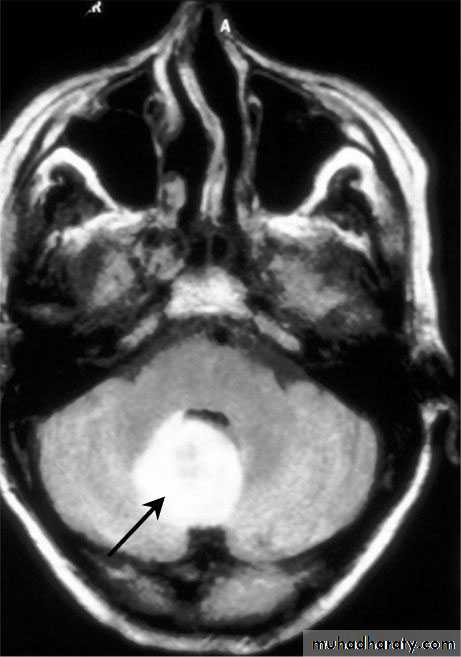

Cerebellar Abscess

Neurosurgery